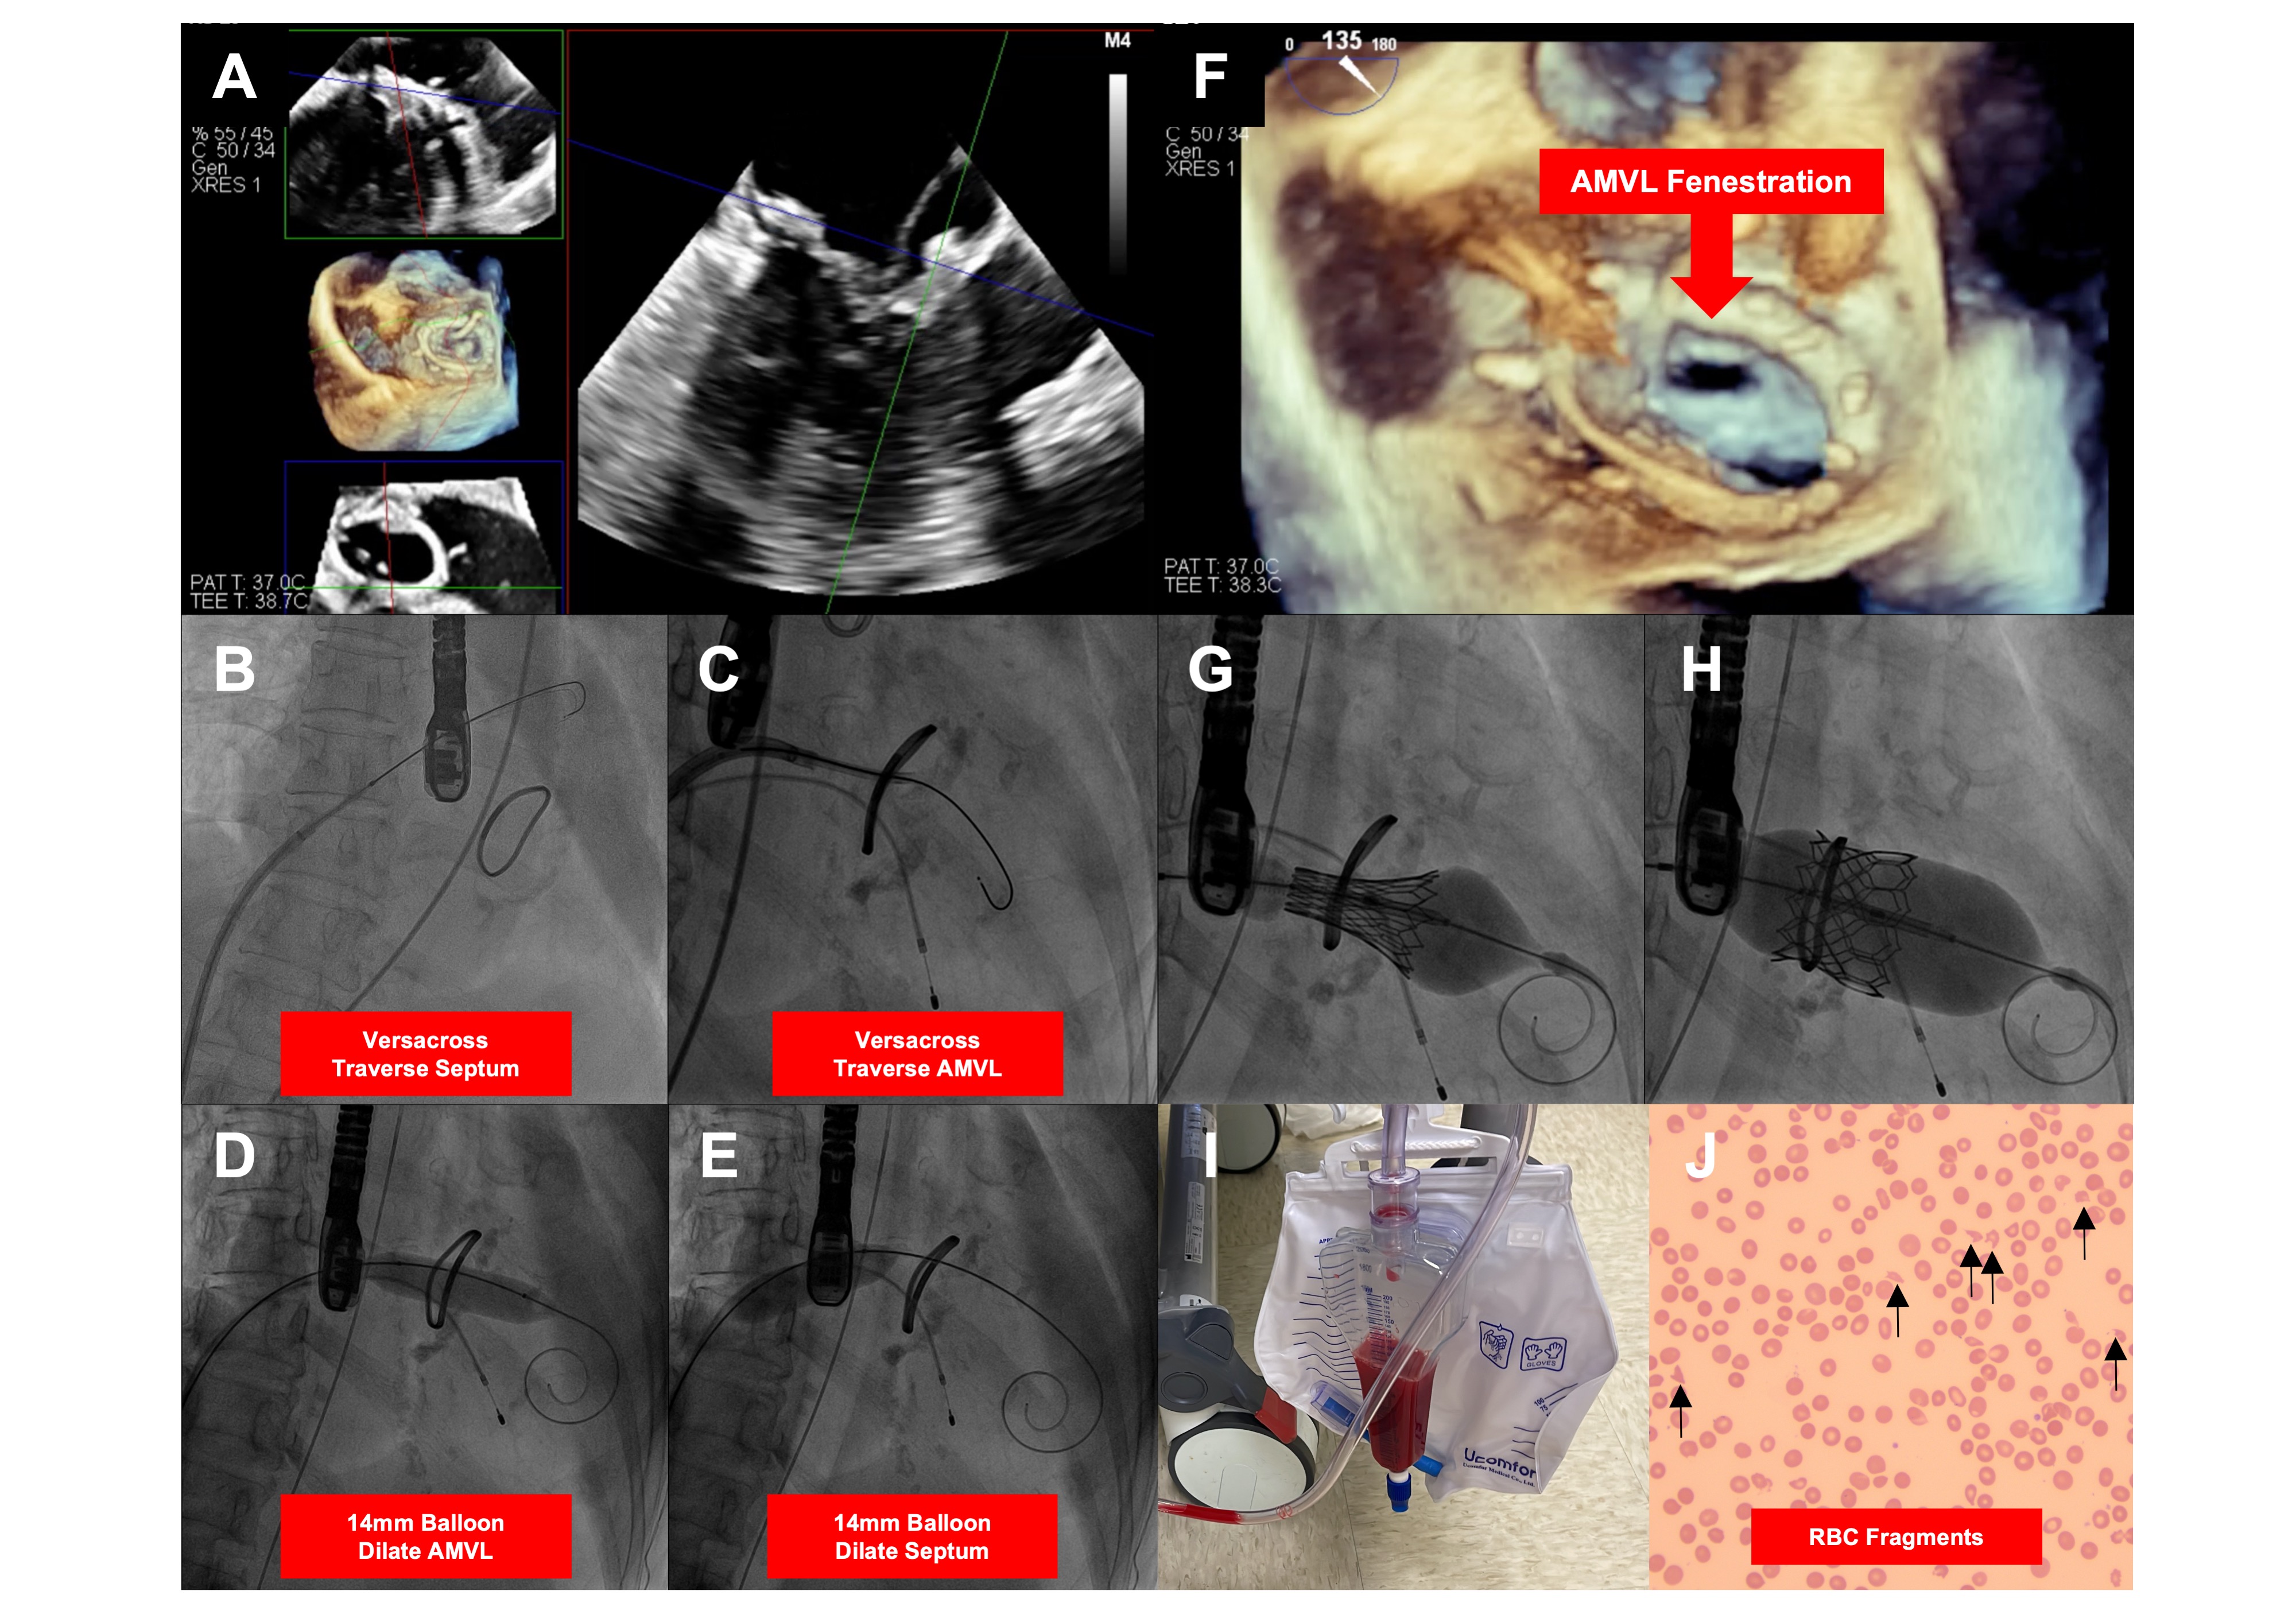

A 74-year-old woman with a previous mitral valve repair (30-mm Carpentier-Edwards Physio II annuloplasty ring; Edwards Lifesciences) developed severe mitral regurgitation. A long anterior mitral leaflet (28.7 mm) conferred a high risk of left ventricular outflow tract (LVOT) obstruction. Transcatheter mitral valve replacement (TMVR) with a simplified “Balloon-Assisted Translocation of the Mitral Anterior Leaflet to Prevent Left Ventricular Outflow Obstruction” (BATMAN) technique was performed.

An intra-aortic balloon pump was preemptively used. A VersaCross (Boston Scientific) traversed the septum and A2 base (Figure A-C). A2 fenestration was dilated with 3- and 14-mm balloons; the 14-mm balloon then dilated the septum (Figure D and E). A provisional approach was adopted, and a buddy wire would only be inserted if needed. The A2 fenestration was traversed easily with a 29-mm SAPIEN 3 (Edwards LifeSciences) without a buddy wire and was deployed. The final LVOT gradient was 7/4 mm Hg.

On postoperative day 1, intravascular hemolysis occurred with hemoglobinuria, anemia, elevated indirect bilirubin, and lactate dehydrogenase (Figure 1I). Blood film showed polychromasia and red cell fragmentation, suggesting microangiopathic hemolytic anemia (Figure 1J). Antiglobulin and anti-ADAMTS13 were negative, and transesophageal echocardiography confirmed only a trivial paravalvular leak. The patient’s blood pressure increased significantly after TMVR, so vasodilators were initiated to reduce the afterload. Clopidogrel, initiated shortly before TMVR, was discontinued, as drug-induced hemolysis could not be ruled out. The hemolysis improved and biochemistry normalized in 2 weeks.